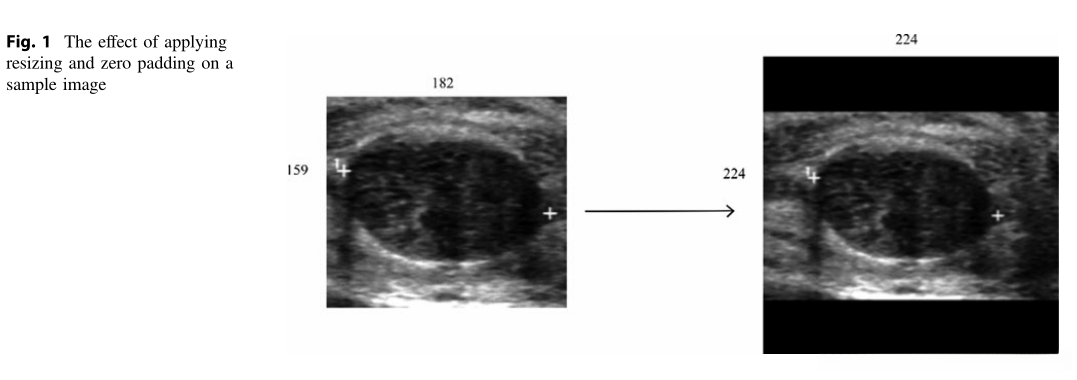

在大多数神经网络架构中,默认假设所有输入图像具有相同的尺寸[11]。基于这一前提,在调整大小时必须以保持原始比例为基础进行尺寸选择。本研究开发了一种算法用于确定原始图像的最佳尺寸,并通过在角落补充零值来构建方阵。通过这种操作方式,在本研究中将图像调整至224×224像素(如图1所示),同时保持了原有的比例关系。此外采用归一化处理措施(Zero Normalization)旨在使数据均值为零、方差为一。这样梯度的变化更为均匀,并且能够有效加速学习过程[12]。